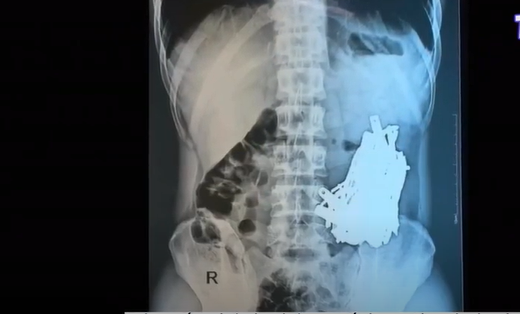

Cứu sống bệnh nhân nuốt hơn 1kg đinh vít. Ngày 1/10, các bác sĩ ở Litva cho biết họ đã lấy ra hơn 1kg đinh vít từ dạ dày của một bệnh nhân nam.

Theo các bác sĩ, người đàn ông này đã bắt đầu nuốt các vật nhỏ bằng kim loại sau khi cai rượu. Bệnh nhân nhập viện ở thành phố cảng Klaipeda trong tình trạng bụng nặng và rất đau đớn.

Những hình ảnh chụp X-quang dạ dày của bệnh nhân cho thấy nhiều mảnh kim loại, trong đó một số có chiều dài lên đến 10cm.

Bác sĩ phẫu thuật Sarunas Dailidenas cho biết: "Trong cuộc phẫu thuật kéo dài 3 giờ với sự kiểm soát bằng tia X, tất cả các dị vật, ngay cả những mảnh nhỏ nhất, trong dạ dày của bệnh nhân đã được lấy ra".

Những hình ảnh về một khay phẫu thuật chất đống đinh vít mà bệnh viện Klaipeda cung cấp đã gây chấn động dư luận.

Phát biểu với báo giới, bác sĩ phẫu thuật Algirdas Slepaviciusvicius tại Bệnh viện Klaipeda cho biết: "Chúng tôi chưa bao giờ gặp bất cứ tình huống nào như vậy".

Hiện sức khỏe bệnh nhân đã trở lại ổn định sau ca mổ.